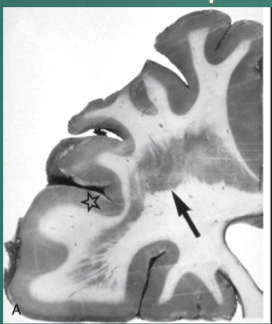

What is your Dx?

Heterotopia (gray matter where there should be white matter - neuronal migration disorder)